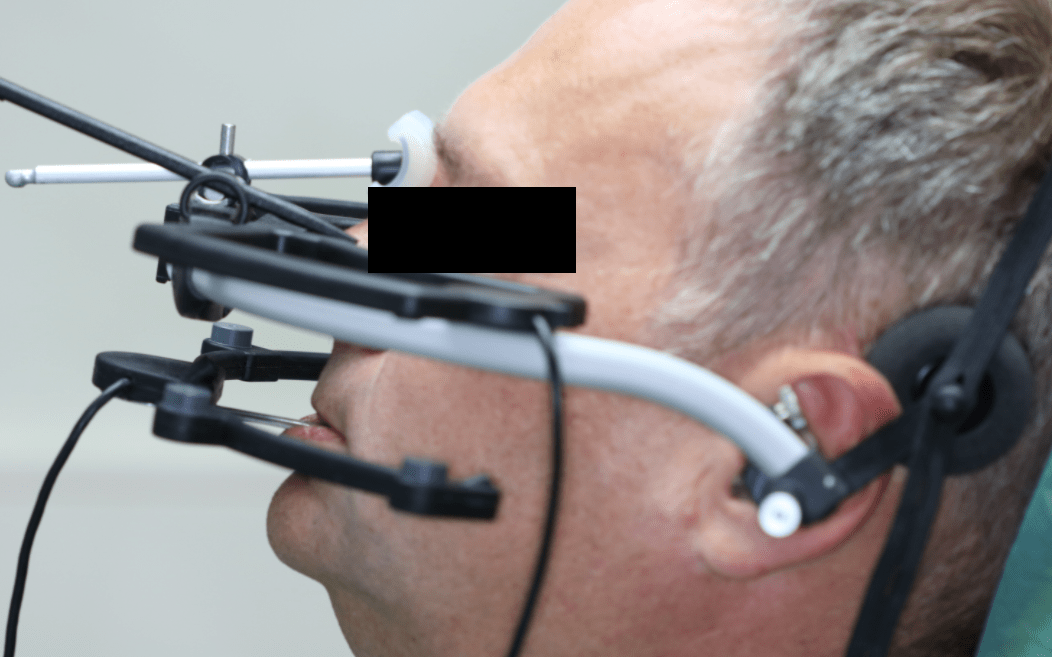

Szükség lehet speciális gyógytornára, egyénre szabott éjszakai sín hordására, akár megfelelő fogszabályozó készülék, illetve fogpótlás elkészítésére is. Ilyen esetekben speciális bemérésre van szükség, amihez úgynevezett nyílhegyrajzoló készüléket, arcívet, pozíciós harapásokat használunk, és segítségül hívhatjuk a legmodernebb, erre a célra létrehozott készüléket: az ARCUSdigmát.

Az állkapocs helyzetének, mozgásának megállapítására, esetleges hibáinak felderítésére az ARCUSdigma rendszer szolgál. A KaVo ARCUSdigma egy elektronikus regisztrációs rendszer, amely 3 dimenziós, ultrahangos méréseken alapul, a páciens egyéni alsóállkapocs-mozgásait méri a koponyához viszonyítva, minden olyan beállítási értéket kiszámít a fogtechnikusok számára, amelyek az artikulátor programozásához és az egyedi, funkcionális fogpótlások készítéséhez szükségesek.

Majd ezt követően arcívvel meghatároztam a felső állcsont koponyához való elhelyezkedését, intraorális rajzolóeszközzel a felső és az alsó állcsont egymáshoz való viszonyát, majd az Arcus Digma készülékkel az individuális mozgáspályákat. Ez mind szükséges ahhoz, hogy egyedi, az egyén számára legkényelmesebb fogpótlás elkészülhessen, melytől jelen esetben páciensünk panaszainak rendeződését vártam.